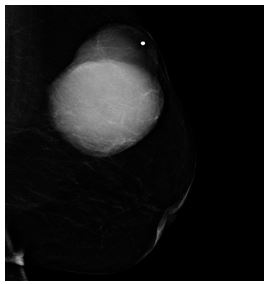

Alamer et al. [13] reported a 66-year-old lady who was known to have hypertension and diabetes mellitus who had presented with a palpable mass within her left breast that was associated with pain over a period of a long time. She did not have any nipple discharge or fever. She also did not have any history of breast trauma, hormone replacement therapy, or a family history of carcinoma of the breast. Her clinical examination showed a large palpable mass which was identified within her left breast with regular borders. Her nipple, areolar, and skin were normal. There was no evidence of palpable lymph node enlargement in her left axilla. Her general examination, systemic examinations and examination of her right breast and right axilla were normal. The results of her investigations including haematology blood tests, biochemistry blood tests, and chest x-ray were normal except elevated serum glucose result. She had a mammogram which showed a large oval and dense mass in the upper outer quadrant of her left breast (see figures 11 and 12). The mass was noted to be lobulated and well-circumscribed in its contours and to have measured 9.2 cm x 7.5 cm. No microcalcification was noted. The nipple, areolar, and skin were normal. The axillary lymph nodes were normal and the right breast was normal. Based upon the mammography examination features of the lump an impression of an usual large dense mass within her left breast was made and coded as BIRAD4A, taking into consideration the age of the patient, and further assessment with ultrasound scan was recommended. The differential diagnoses that were considered included: Phyllodes tumour, pseudo-angiomatous stromal hyperplasia (PASH), and well circumscribed carcinoma of the breast.